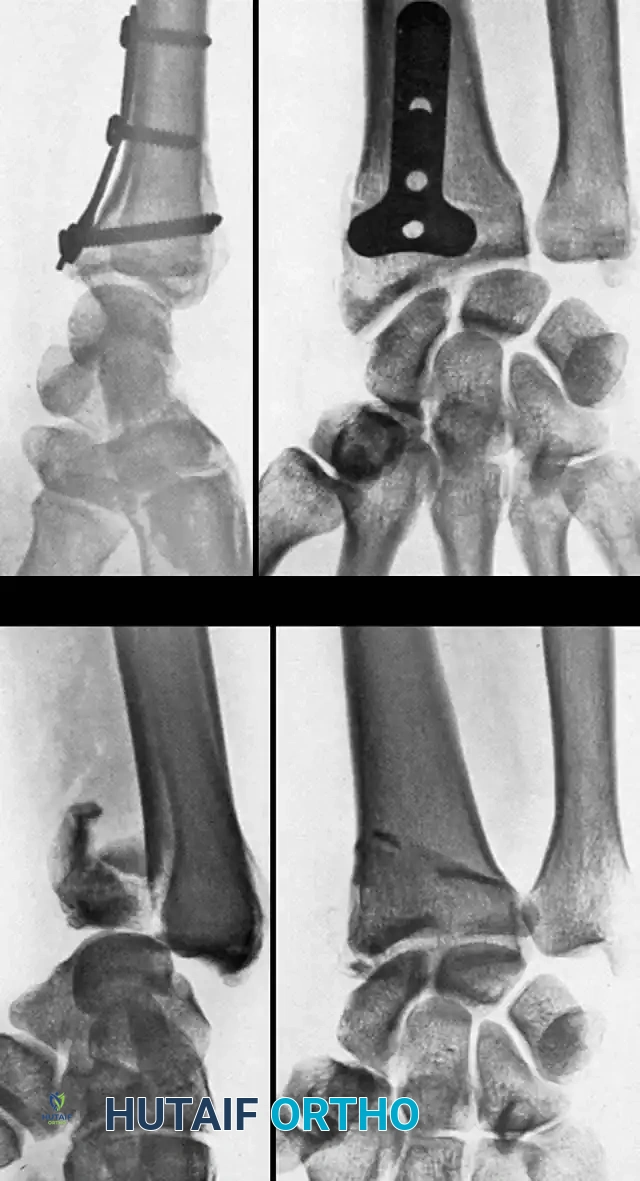

Fig. 54-103 A and B, Four-part type III distal radial fracture treated by open reduction, internal fi xation of intraarticular component, iliac bone grafting, and external fi xation. C and D, Follow-up radiographs at 5 weeks (C) and 3 years (D) show anatomical restoration of joint surface, maintenance of radial length, and absence of degenerative changes. (From Fernandez DL: Fractures of the distal radius: operative treatment, Instr Course Lect 42:73, 1993.)

Fig. 54-103 A and B, Four-part type III distal radial fracture treated by open reduction, internal fixation of intraarticular component, iliac bone grafting, and external fixation. C and D, Follow-up radiographs at 5 weeks (C) and 3 years (D) show anatomical restoration of joint surface, maintenance of radial length, and absence of degenerative changes.